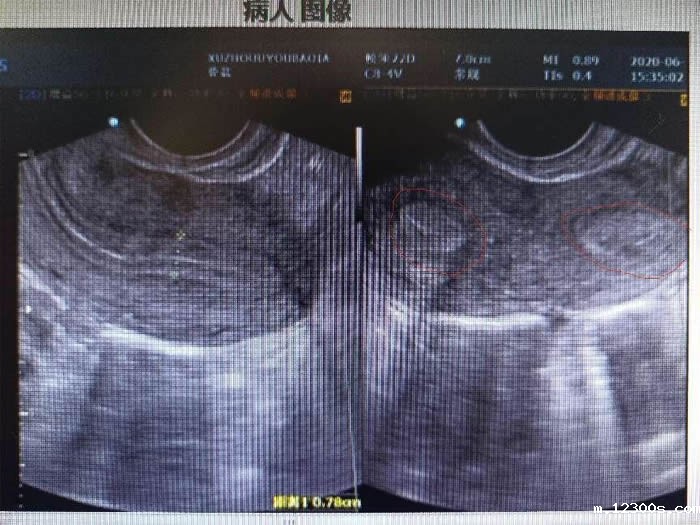

一年前,陈女士因为结婚两年未孕、痛经严重来到医院就诊。彩超检查后发现陈女士子宫畸形,单角子宫合并残角子宫II型,残角子宫有功能内膜,与单角子宫宫腔不相通,每次月经经血逆流导致陈女士腹痛难忍,日常还伴有同房的性交痛。